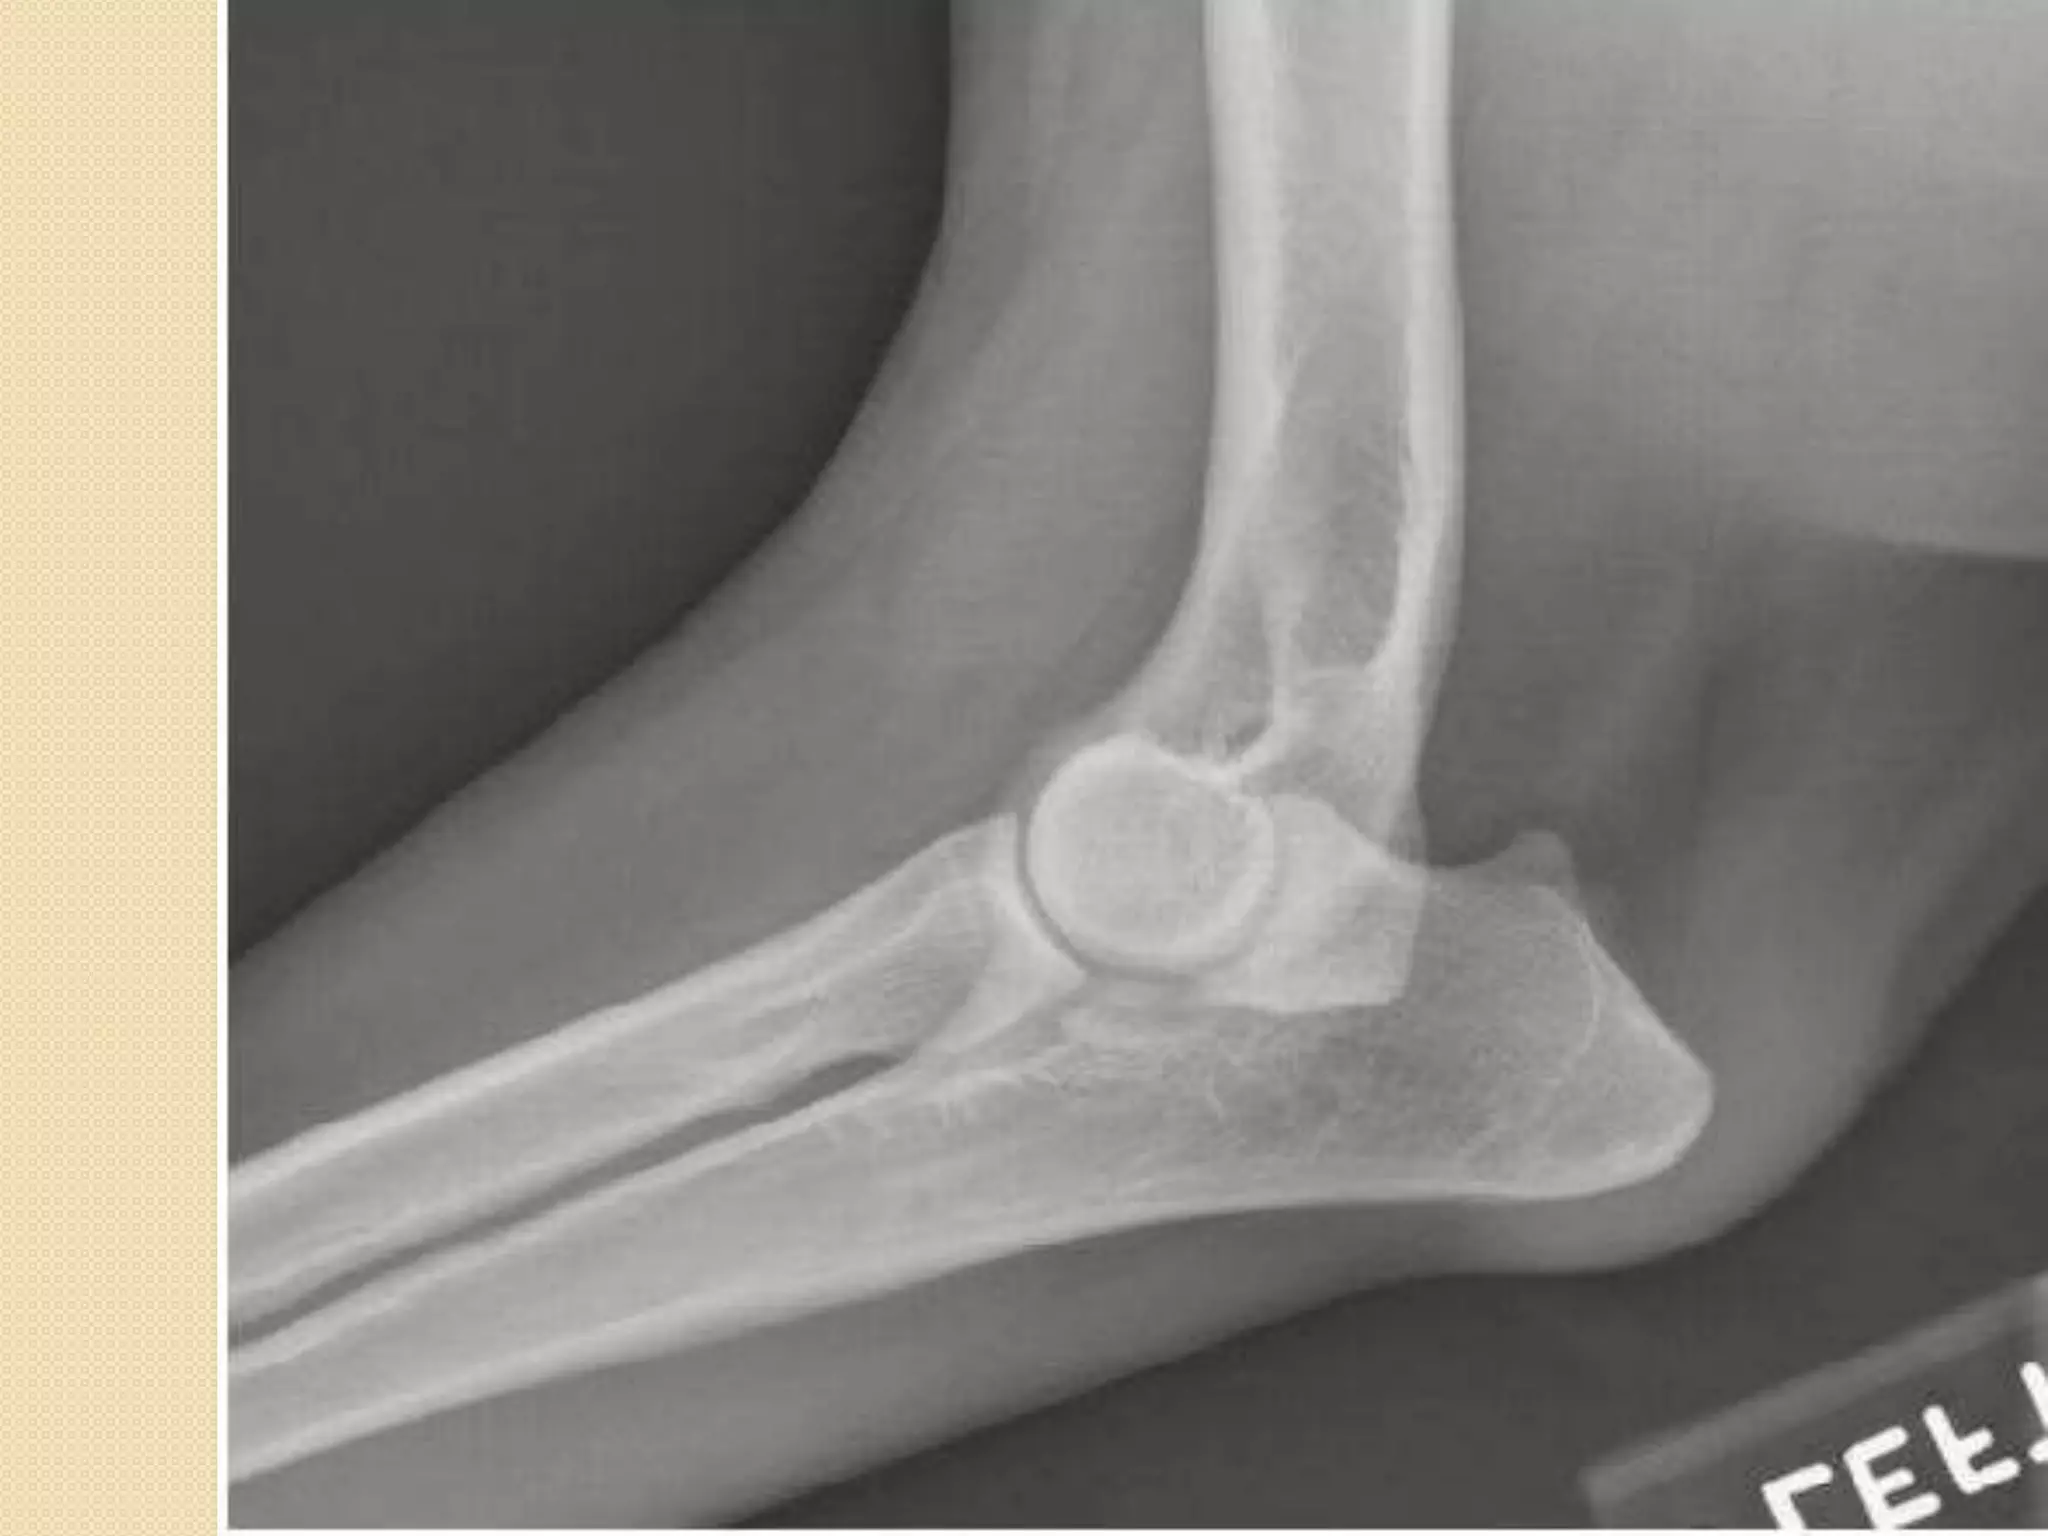

Humerus:

-It is a long bone which is called also the brachium-The head of the humerus with the glenoid cavity

of the scapula form the shoulder joint.

-The presence of supratrochlear foramen

D=supratrochlear foramen

Elbow joint: